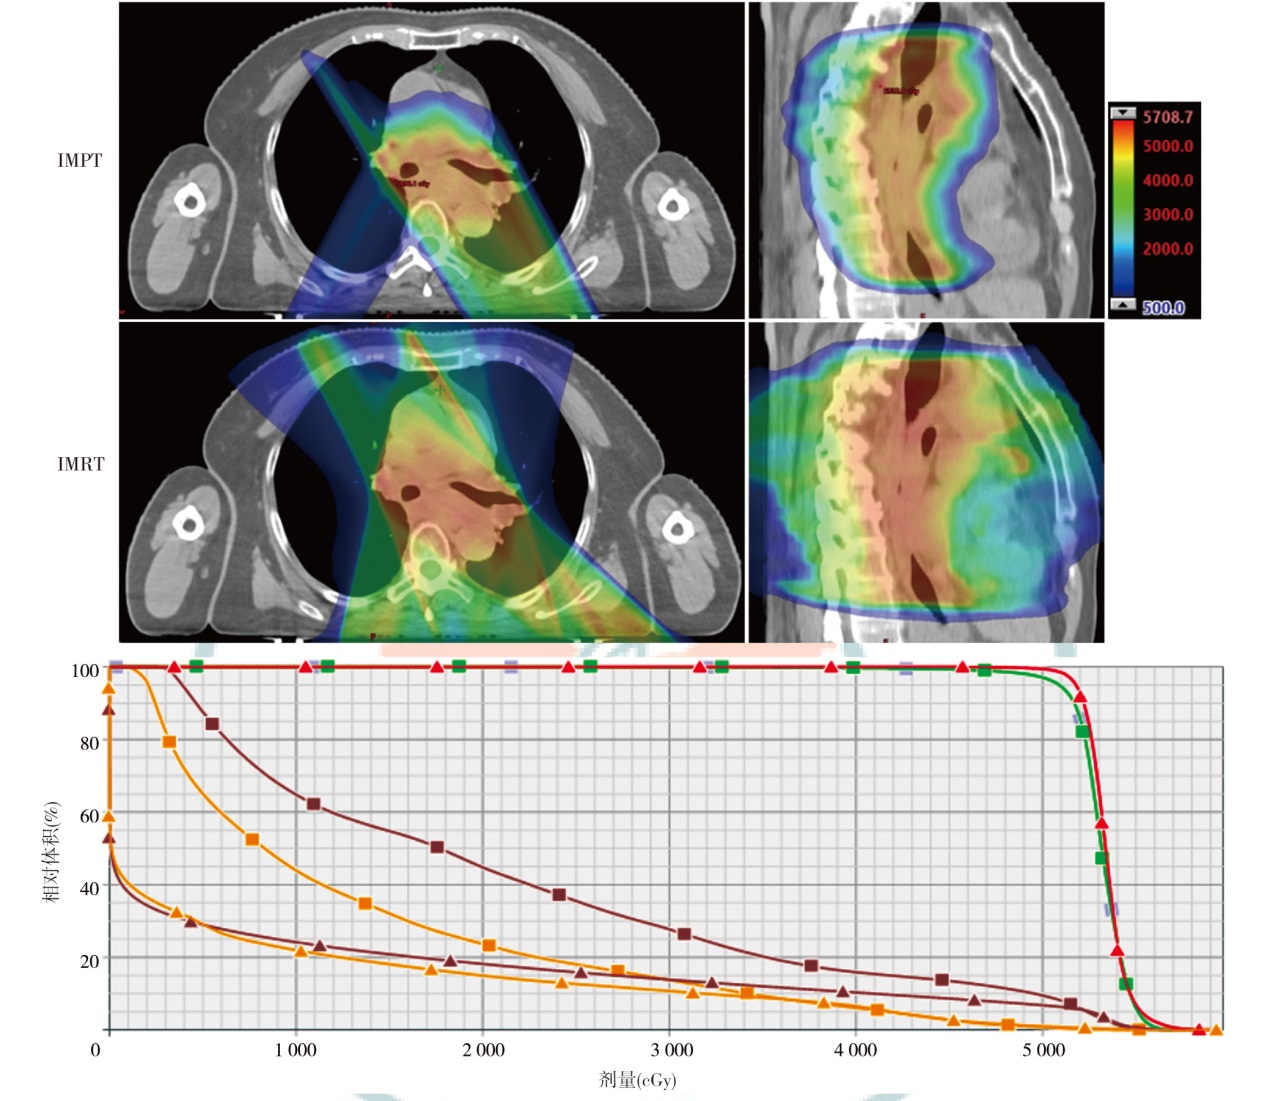

目的探讨食管癌质子放疗计划与光子放疗计划的剂量学特点。方法以山东省肿瘤防治研究院(山东省肿瘤医院)2024年1月至2024年4月收治的需行放疗的4例食管癌患者为研究对象,靶区分别为颈段、胸中段及全段食管,以及涉及的淋巴引流区。根据临床靶区和危及器官限值的要求,分别设计质子调强放疗(IMPT)和光子固定野调强放疗(IMRT)两种放疗计划。比较两种计划的靶区适形指数(CI)、均匀性指数(HI)、梯度指数(GI)以及危及器官的剂量学差异,通过评估体内10%、30%和50%的剂量体积比较患者体内额外的剂量沉积。结果4例患者IMPT计划的HI(0.12、0.10、0.06和0.08)、GI(3.11、3.21、2.43和2.72)、CI(0.59、0.60、0.77和0.72)均小于IMRT计划(HI分别为0.15、0.13、0.10和0.11,GI分别为4.52、5.14、3.09和3.92,CI分别为0.81、0.77、0.91和0.85)。与IMRT计划相比,4例患者IMPT计划的全肺受量指标中,V5分别下降34.1%、55.0%、79.7%和60.3%;V20分别下降48.3%、43.9%、65.8%和40.8%,Dmean分别下降43.4%、57.2%、76.2%和45.4%;心脏V30分别下降36.2%、45.3%、40.1%和52.4%,Dmean分别下降96.6%、57.9%、58.5%和55.3%。对于胸中下段靶区,肝脏在IMPT计划中得到明显保护(Dmean较IMRT计划下降76.0%)。患者体内额外剂量沉积方面,IMPT计划中10%剂量体积减少了45.0%~61.4%;30%剂量体积减少了41.2%~61.8%;50%剂量体积减少了34.8%~61.6%。结论通过比较4例食管癌的IMPT和IMRT计划相关剂量学参数,IMPT计划在降低肺组织、心脏以及肝脏器官的剂量方面具有优势,并能够减少患者体内额外剂量沉积。

ObjectiveTo explore the dosimetric characteristics of proton radiotherapy plan and photon radiotherapy plan for esophageal cancer.MethodsFour patients who were admitted to Shandong Cancer Hospital and Institute from January 2024 to April 2024 with esophageal cancer (cervical, middle thoracic and total esophageal tube, as well as the lymphatic drainage areas involved) and required radiotherapy were selected as the research subjects. Intensity modulated proton therapy (IMPT) and intensity modulated radiation therapy (IMRT) plans were designed respectively based on the clinical target volume and the dose constraints for organs at risk (OARs). Dosimetric parameters, including conformity index (CI), homogeneity index (HI), gradient index (GI) for target coverage, as well as OARs dosimetric parameters were evaluated. The volume of additional dose deposition in the body was compared by assessing regions receiving 10%, 30%, and 50% of the prescription dose.ResultsFor all four cases, IMPT plans yielded lower HI values (0.12, 0.10, 0.06, and 0.08) than IMRT plans (0.15, 0.13, 0.10, and 0.11), and the GI values of IMPT plans (3.11, 3.21, 2.43, and 2.72) was lower than IMRT plans (4.52, 5.14, 3.09, and 3.92). Moreover, the CI of the IMPT plans (0.59, 0.60, 0.77, and 0.72) was inferior to IMRT plans (0.81, 0.77, 0.91, and 0.85). Compared with the IMRT plans, in the whole lung dose indicators of the IMPT plans for the 4 patients, V5decreased by 34.1%, 55.0%, 79.7% and 60.3%, respectively; V20decreased by 48.3%, 43.9%, 65.8% and 40.8%, respectively, and Dmeandecreased by 43.4%, 57.2%, 76.2% and 45.4%, respectively. V30of the heart decreased by 36.2%, 45.3%, 40.1% and 52.4%, respectively, and Dmeanof heart decreased by 96.6%, 57.9%, 58.5% and 55.3%, respectively. For the middle and lower thoracic target area, the liver was significantly protected in the IMPT plan (Dmeandecreased by 76.0% compared with the IMRT plan). In terms of the additional dose deposition in the patient's body, IMPT plans reduced the volumes receiving 10%, 30% and 50% of the prescription dose by 45.0%-61.4%, 41.2%- 61.8% and 34.8%-61.6%, respectively, compared with the IMRT plans.ConclusionsBy comparing the dosimetric parameters of IMPT and IMRT plans for 4 cases of esophageal cancer, the IMPT plans have advantages in reducing the doses to lung tissue, heart, and liver, and can also reduce additional dose deposition in the patient's body.